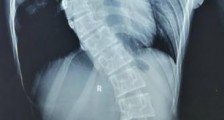

- 重庆12岁女童脊柱弯曲如“S型” 手术后终于“挺直腰杆”

- 中新网重庆4月3日电 (韩璐

袁儒青)拥有“S型”身材,是很多花季少女的梦想。但12岁的女孩婷婷(化名),却因为自己的脊柱弯曲如“S型”,被人笑话。记者3日从重庆医科大学附属...